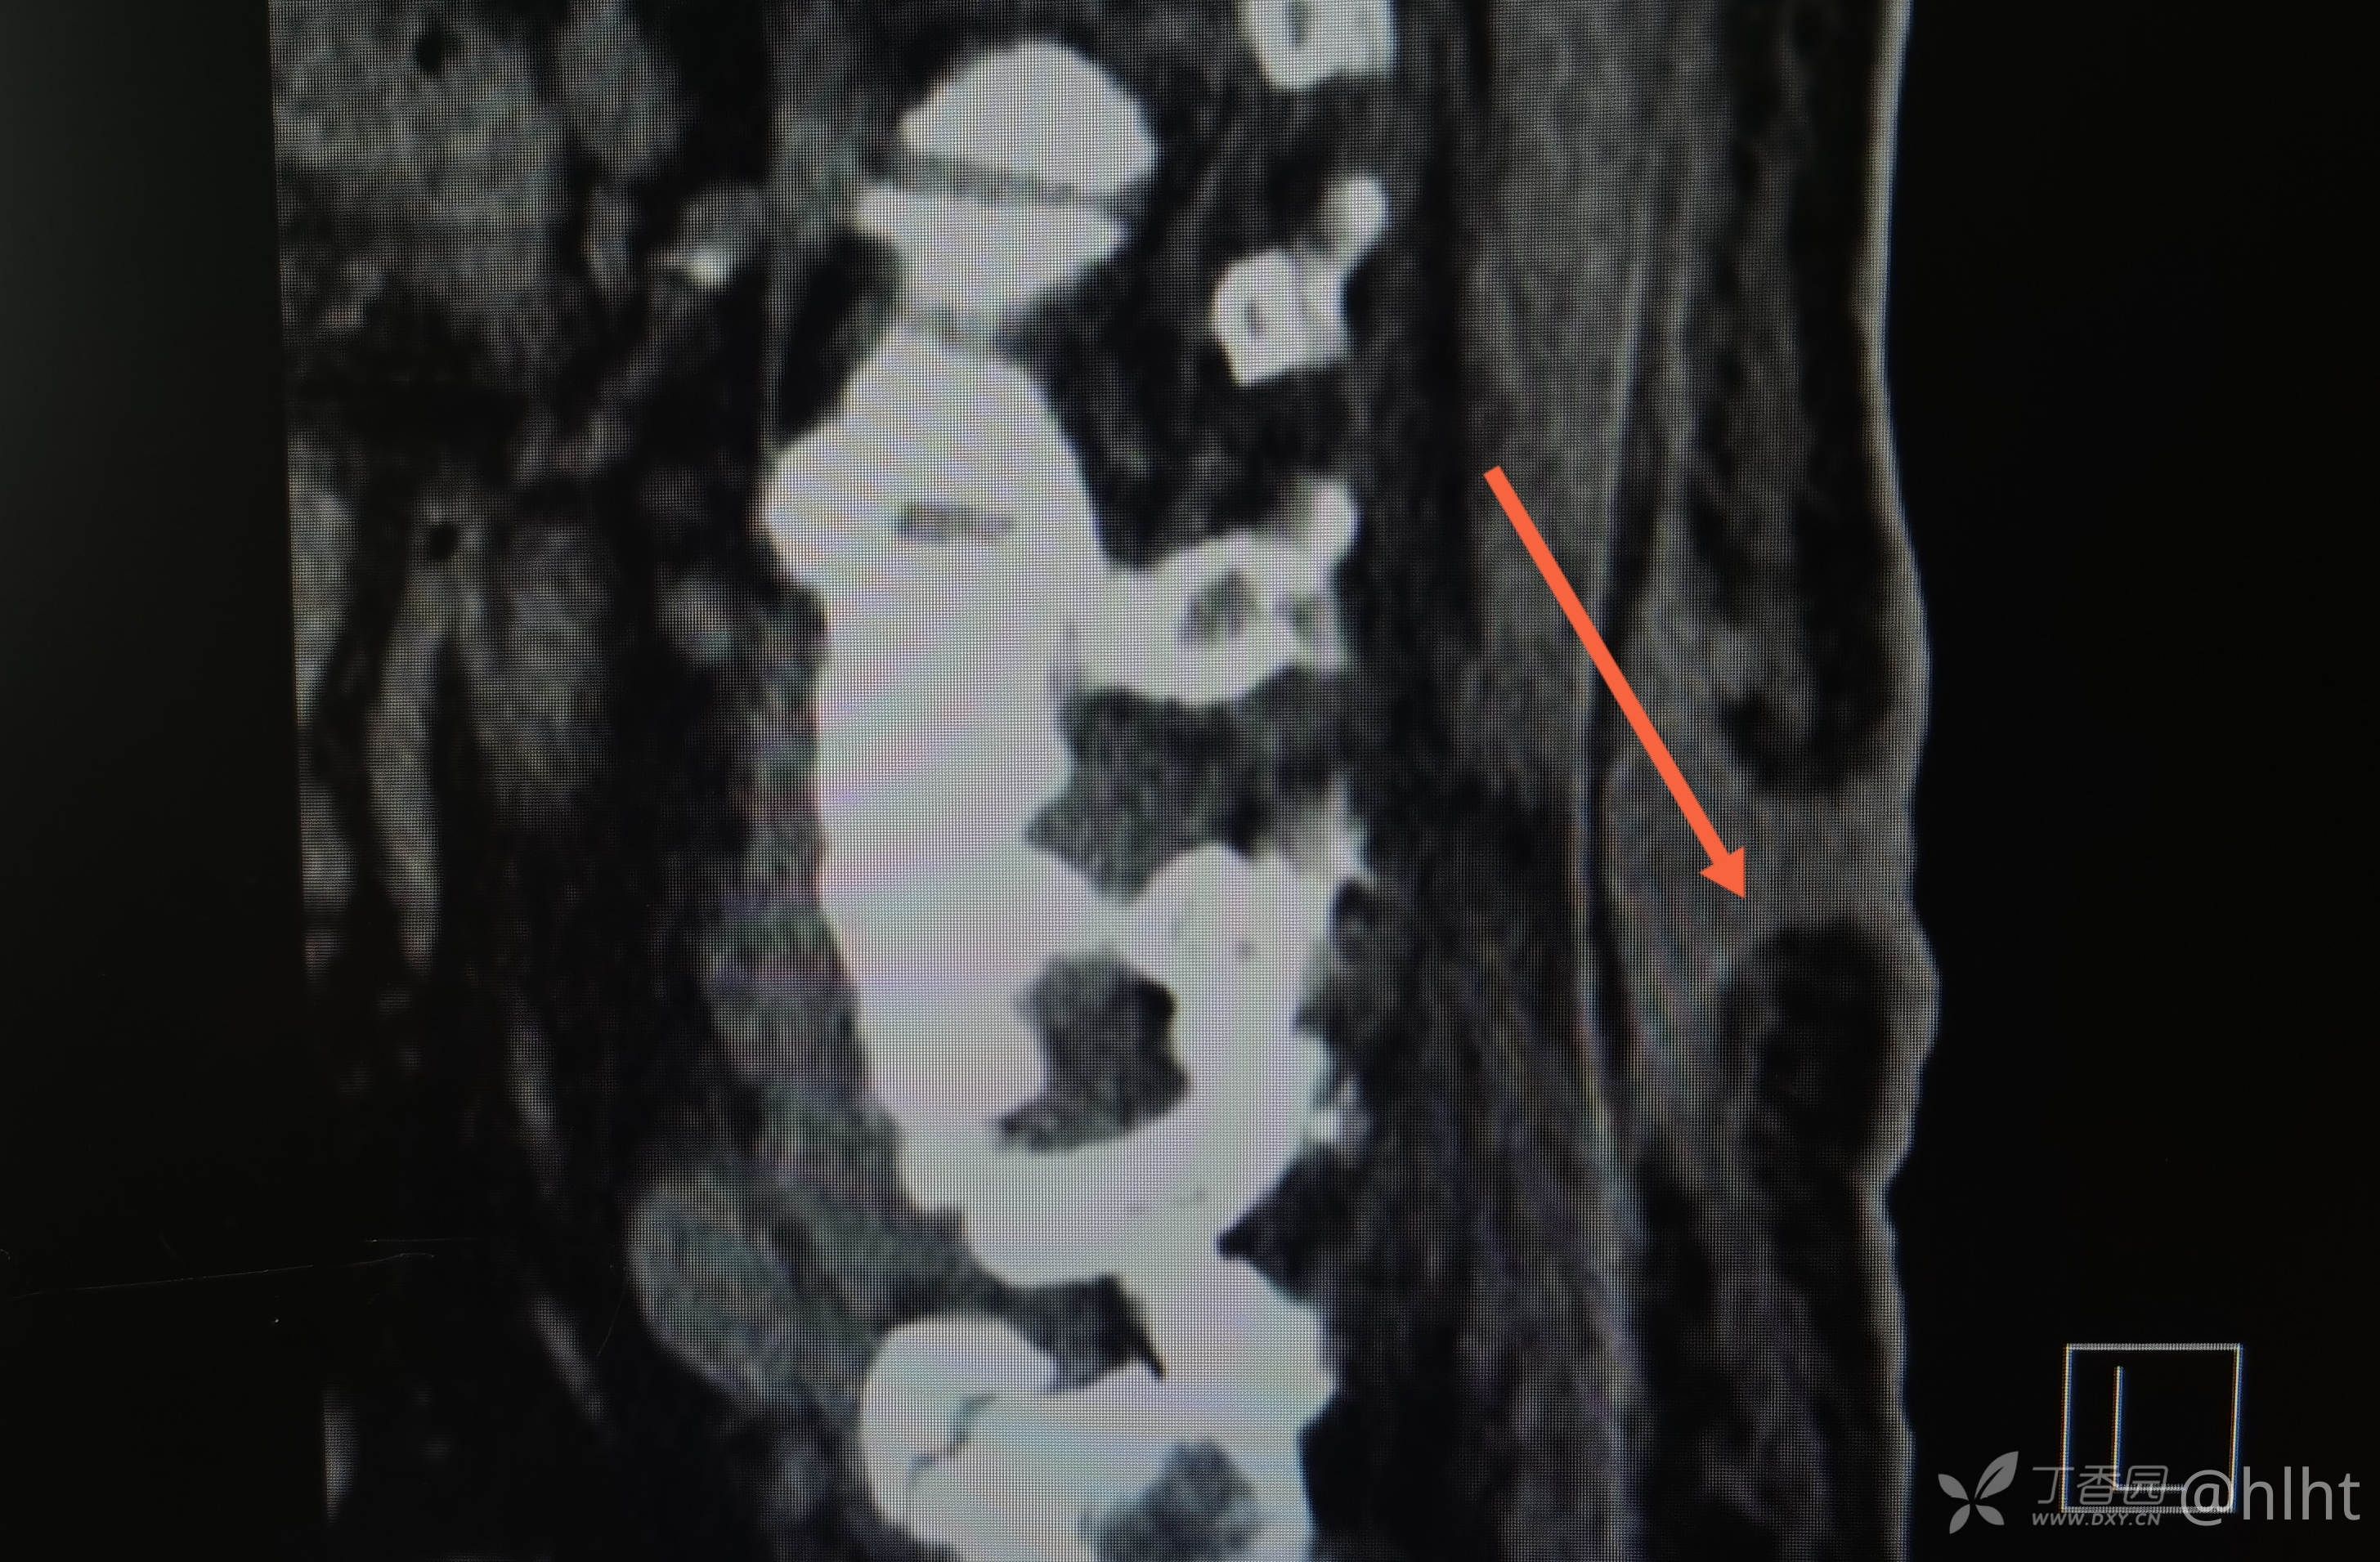

诊断:1.左侧腰大肌、髂腰肌脓肿 :结核? 2.2型糖尿病 3.高血压2级